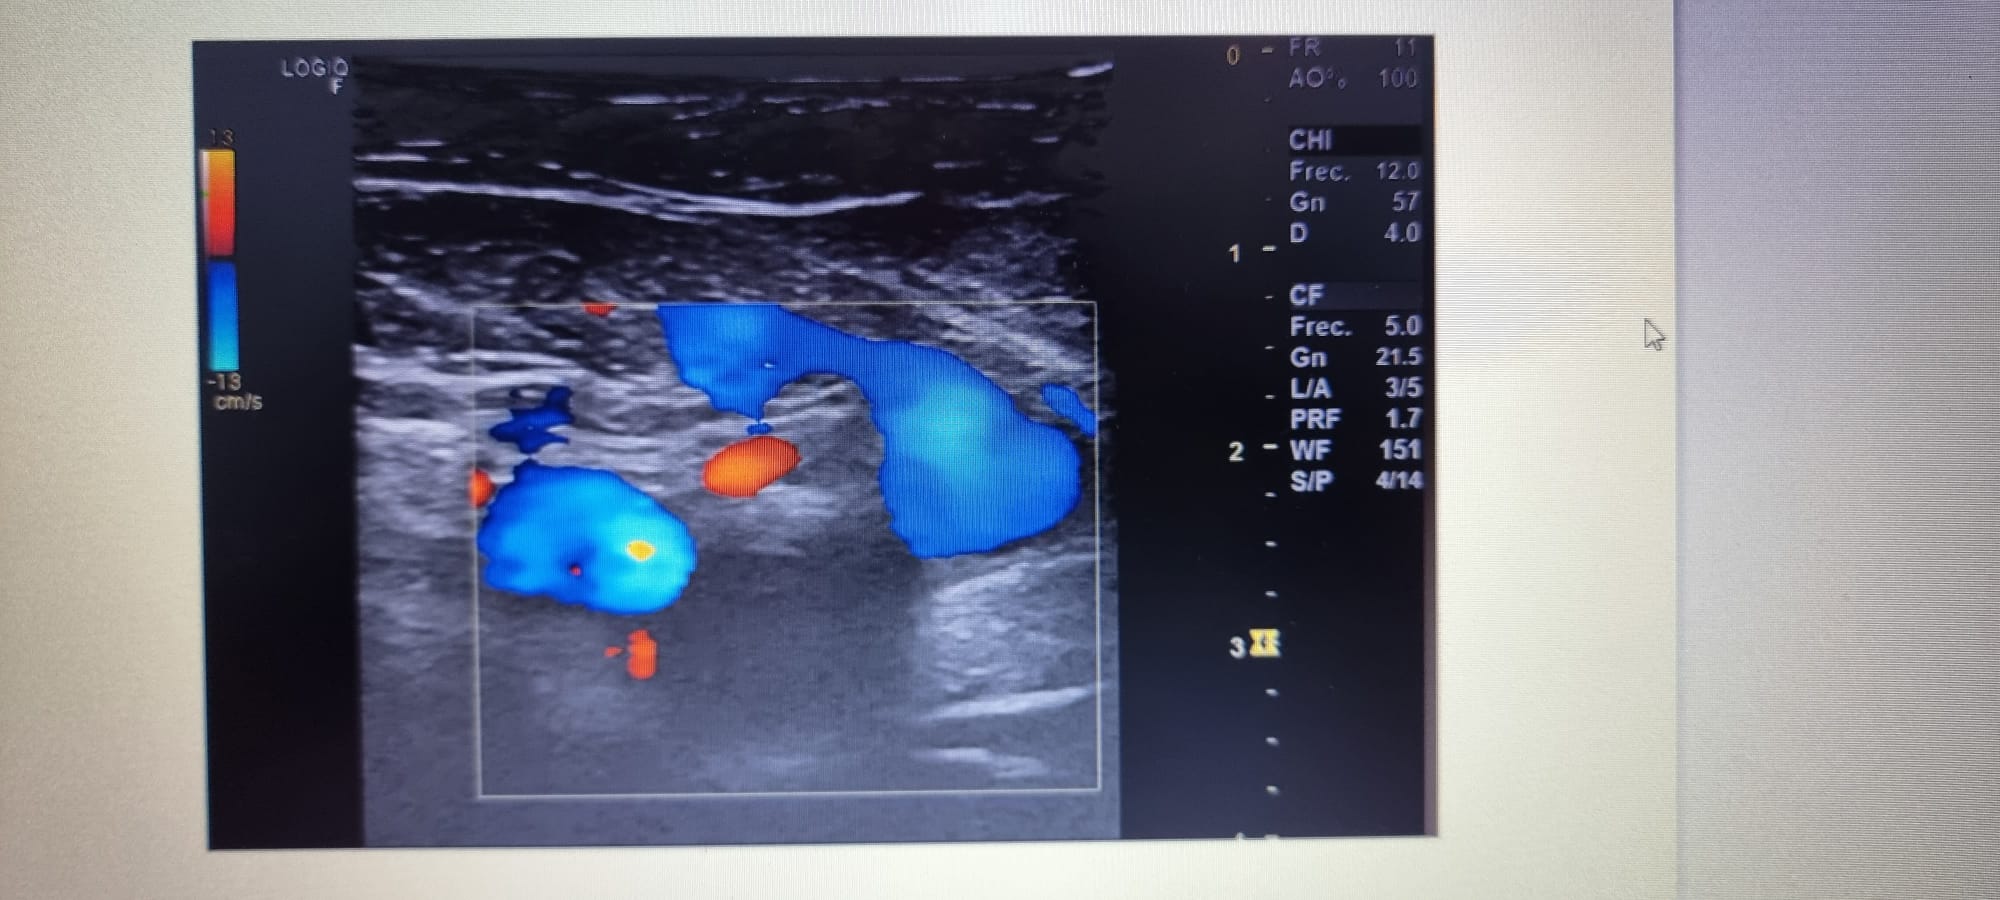

Ecografia en Urg hospital: ocupación parcial de la luz de las venas femoral común y segmento proximal de la femoral superficial, ocupación completa de la luz en segmentos medio-distal de la femoral superficial y vena poplitea.

Se confirma con Doppler venoso de MID urgente y se ingresa en MI.